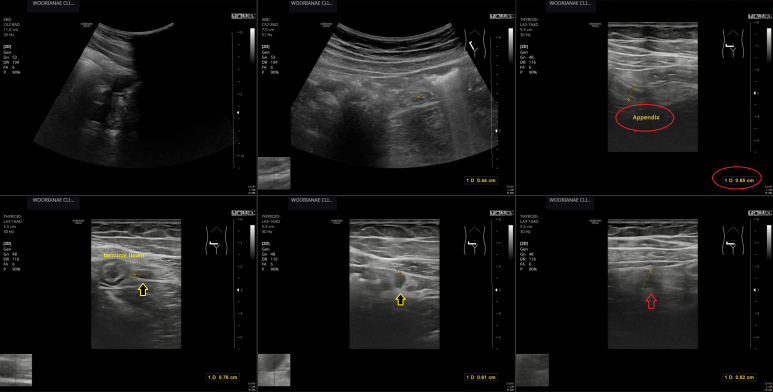

"심하게 가스찬다." 팽만감 과 이곳저곳 복통, 그러나 우하복부 압통, 림프절염? 충수돌기염? 약제치료 후 추적 계획

30대 중반 남자 4일전부터 팽만감, 가스차는 느낌이 심하다. 아랫배, 우측배, 윗배 누르면 아프고... 조금만 먹어도 가스찬 느낌이 심하다. 2일전부터 약간 호전 신체검사상 우하복부에서 약간 상방으로.. 압통이 명확 게실염 감별 확인,...